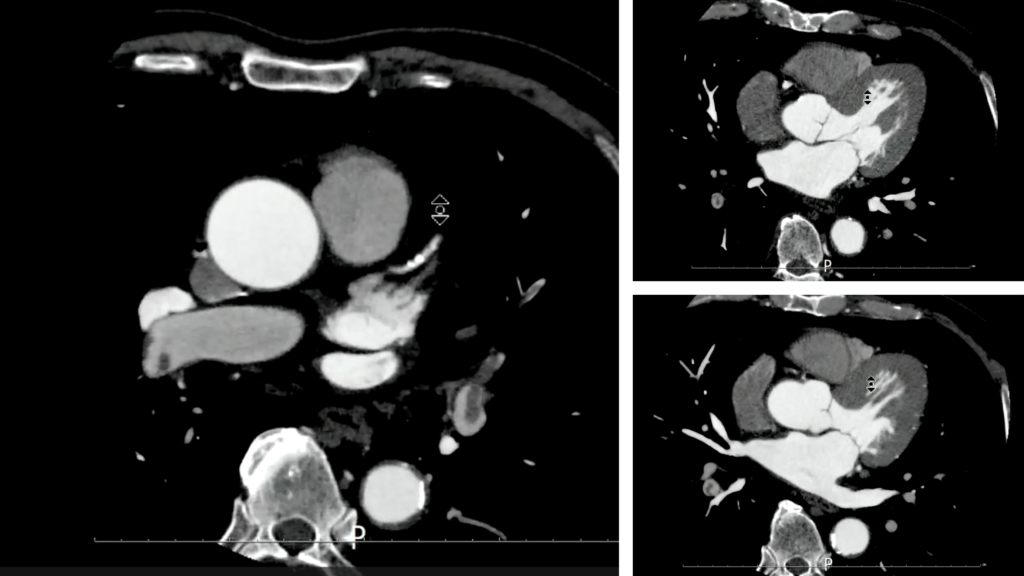

- CT画像

上行動脈にROIを置いたボーラストラッキングにてイオパミロン370 造影剤注入速度5.0ml/sec 造影剤量65mlにて撮影された画像です。

その他に何か所見はきづきましたか?

両側の肺動脈に造影不良域(filling defect)を認めます。

肺動脈塞栓(PTE)を疑う画像です。

この症例では撮影者がリアルタイムにこの所見に気づき、すぐ放射線科医に報告し肺動脈と深部静脈を観察するために胸腹部の追加撮影を行いました。